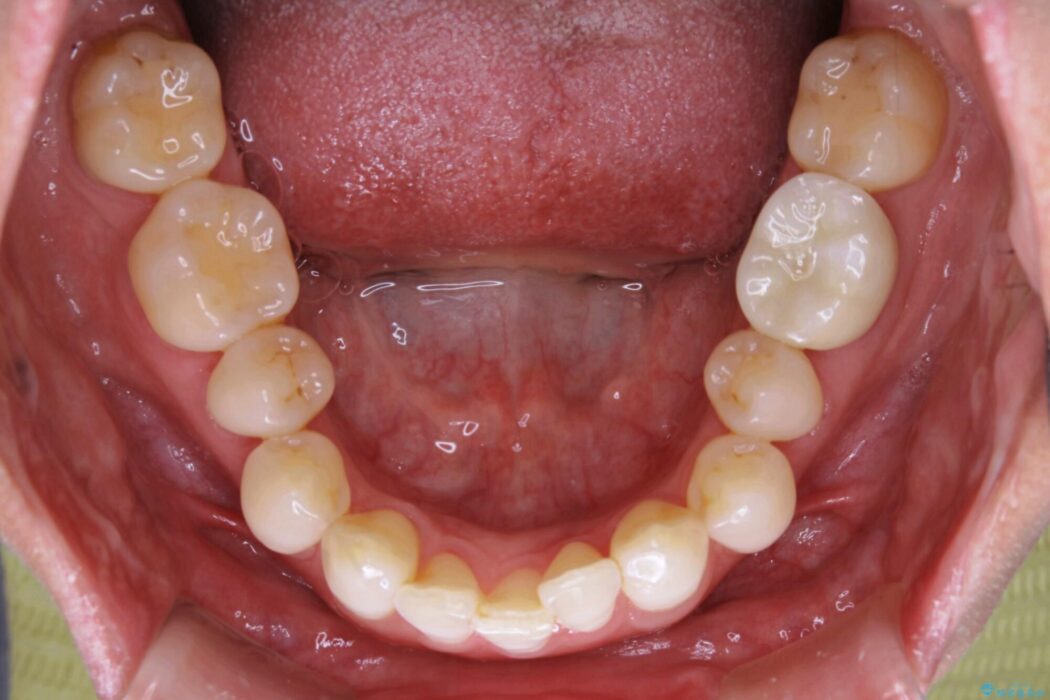

前歯のガタつきの治療を目的に来院されました。

主訴としては矯正治療にて歯列を整えることでした。

治療計画を立てる上で詳しく精密検査をしたところ、左下の6番目の歯につきまして治療が必要な状態であることが分かり、かぶせ物を外し、内部を確認しました。

結果としては深い部分で根が破折してしまっていました。